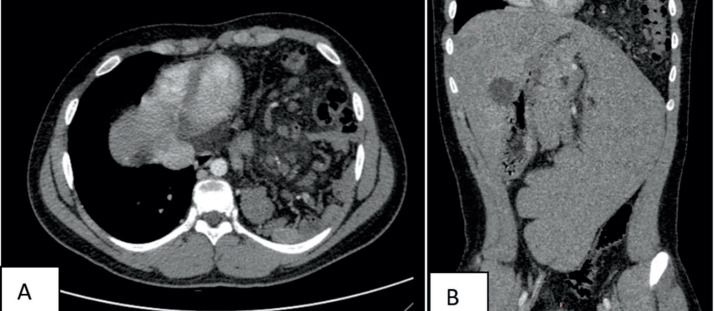

Objective: The aim of this case report was to present 15-year-old male with vomiting and mild upper abdominal pain who had mild epigastric tenderness with no guard and an IV grade splenomegaly caused by Congenital Diaphragmatic Hernia. Case presentation: We report a case of left portal hypertension and hypersplenism in an adolescent with congenital diaphragmatic hernia. Typical clinical presentations include abdominal pain, respiratory symptoms, or intestinal obstruction in incarcerated diaphragmatic hernia. Additionally, some uncommon symptoms reported in literature include gastrointestinal bleeding as a result of portal hypertension, thrombocytopenia due to hypersplenism, and acute pancreatitis.

Conclusion: The treatment has released the obstruction in the splenic vein and reduce returned collateral gastric blood flow. Splenectomy should be considered based on many factors, such as anatomic anomalies or the degree of hypersplenism and portal hypertension. This is a rare clinical entity with only a few cases that have been reported in the literature.